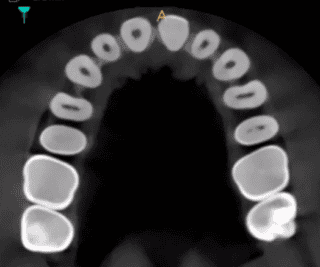

This is why we have a CBCT scanner - it tells us exactly where nerves are in relation to the tips of the roots..... planning is essential for these cases